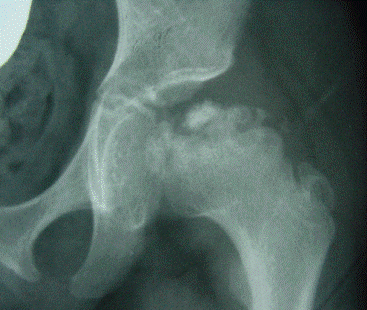

LEGG PERTHES

Enfermedad de Legg Perthes